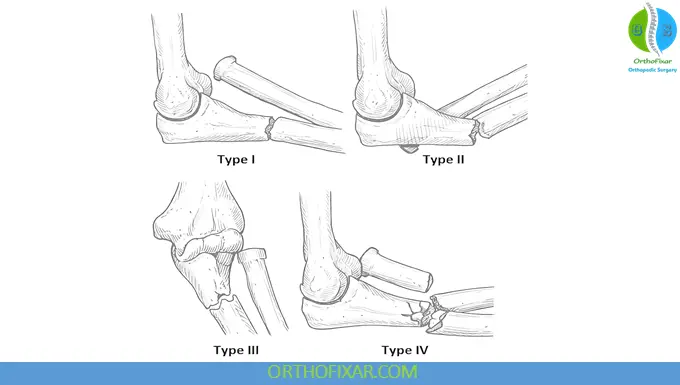

Monteggia Fracture Classification (Bado Classification)

Type I (Most Common)

- Anterior dislocation of radial head

- Fracture of ulna with anterior angulation

Type II

- Posterior or posterolateral dislocation of radial head

- Ulna fracture with posterior angulation

Type III

- Lateral dislocation of radial head

- Metaphyseal fracture of ulna

Type IV

- Fractures of both radius and ulna

- Radial head dislocation